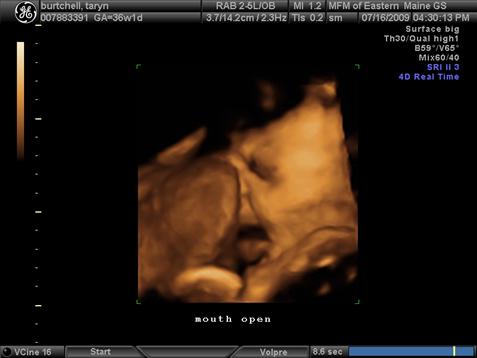

So yesterday i had my 3D sono and she is head down and ready to go but she is right next to the placenta... is that bad that the placenta is that low? My OB hasn't received the report of the sono yet (probably sometime today). Will this cause a problem?

I included sono pic for a better idea---her face is right next to the placenta kinda pushed into her nose. Image Attachment(s):